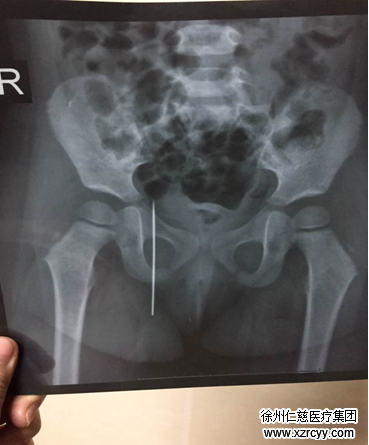

家住贾汪的欣欣今年2岁半,活泼可爱,聪明机灵。和其他小孩子不同的是:欣欣是一名留守儿童。早在欣欣7个月大还在嗷嗷待哺时,父母就前往深圳打工,欣欣一直由其爷爷奶奶照顾。昨天上午,欣欣奶奶在家缝补被子,补好被子上的一个洞,就把工具收了回去,却忘了床上那根又粗又长的缝被针。“当时我和她爷爷不在她身边,只知道她在床上看电视,也没喊没哭,到了晚上我看她走路一拐一拐的,就问她怎么回事,她也说不清楚,就说屁股痛。”眼见着欣欣闹腾着屁股痛,奶奶也急了,连夜带欣欣来到必威官方首页官网betway检查,结果令所有人都大吃一惊:X光显示欣欣的右臀处扎入了一根长约7厘米的缝被针!

betway在线登陆手外科一病区李甲主任介绍,诸如“绣花针、针灸针、缝被针”这类异物取出难度较高,因针体较细,在人体内的位置会不断“游离”。再者臀部脂肪和肌肉较多,更加难以取出,经过C型臂定位与反复探查,医生终于成功取出欣欣右臀里的缝被针。最后李甲主任提醒各位父母,锐利器物与各种对孩子有安全威胁的东西,家长一定要仔细收好!